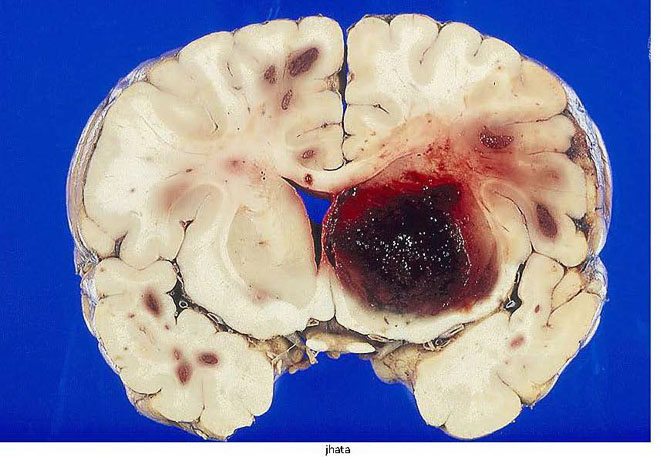

また、動脈硬化によって弱くなった脳動脈が破れて脳出血を起こします(図18)

図18 大脳出血